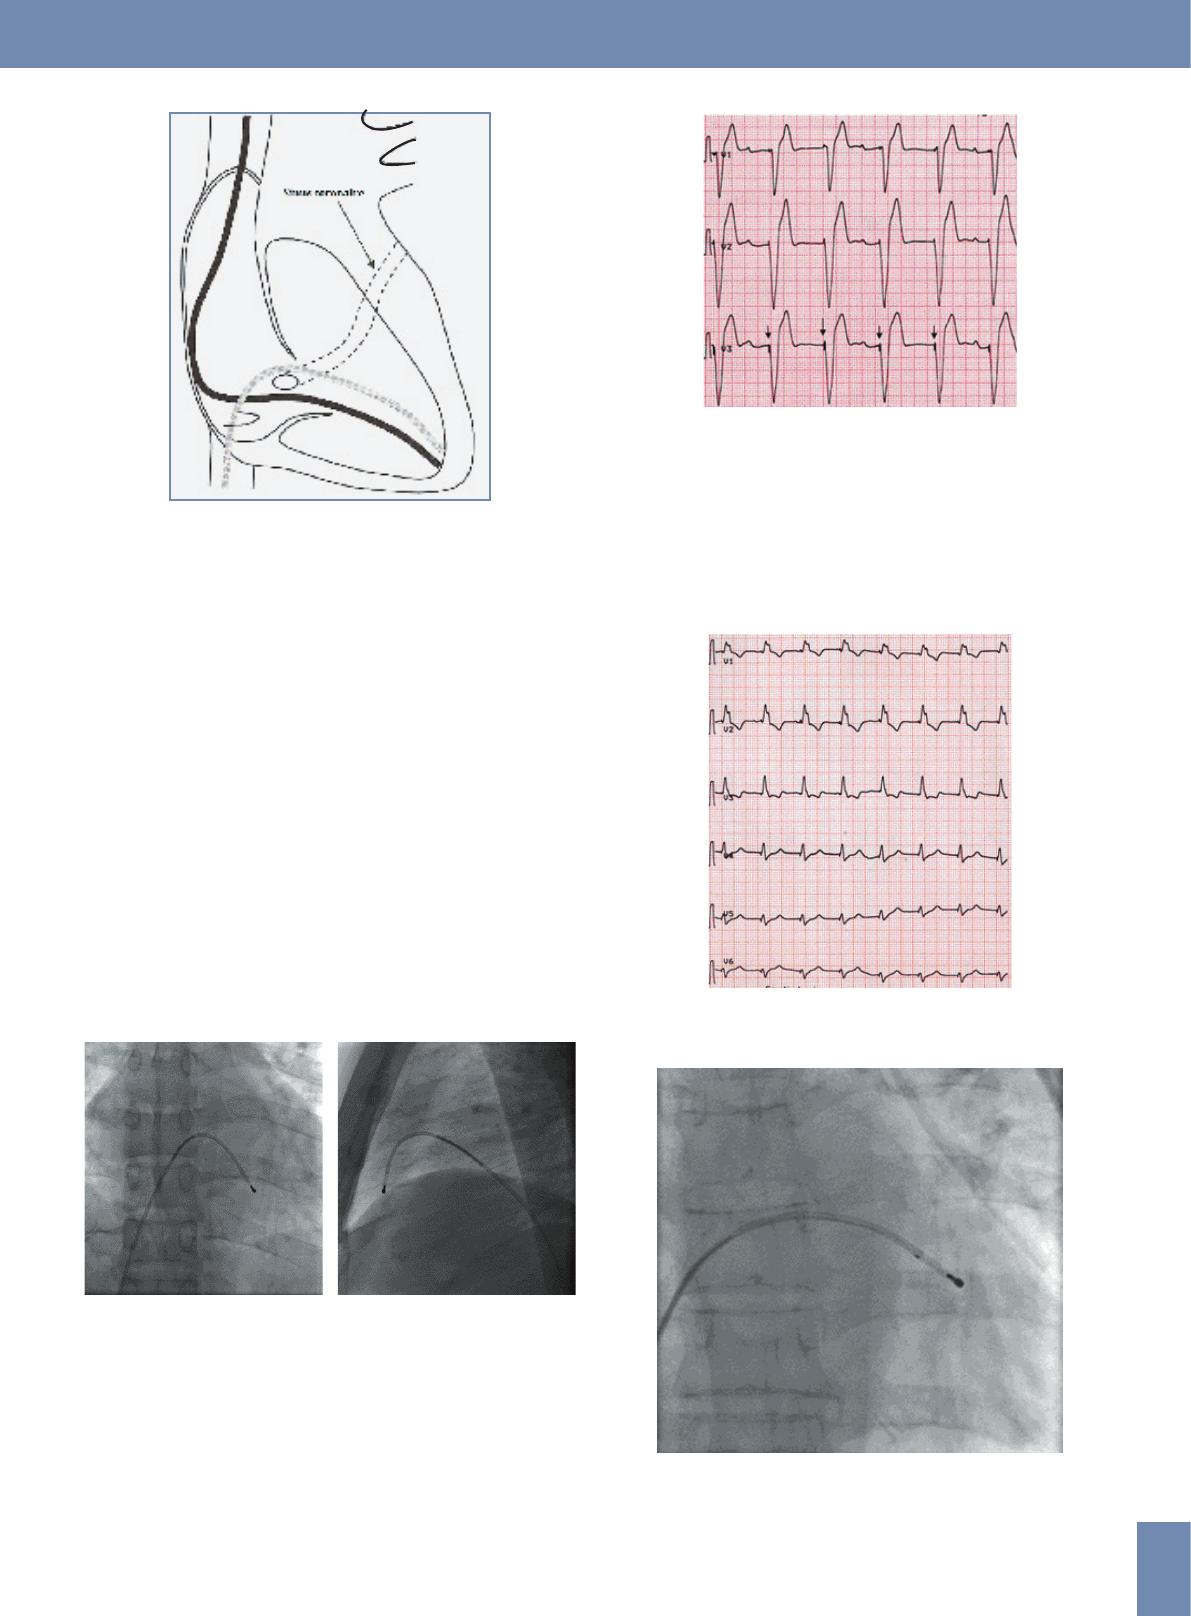

veine sous-clavière ou la veine fémorale (figure 2).

Figure 2. Position de la sonde de stimulation en fonction de l’abord

veineux jugulaire, sous claviculaire (en noir) ou fémoral (gris).

Dans le ventricule droit, la sonde est positionnée au

niveau de l’apex par des mouvements d’avancement,

de retrait et de rotation. Le contrôle de la stabilité de la

sonde est réalisé sous scopie en demandant au patient de

respirer profondément et de tousser (figure 3).

A B

Figure 3. Aspect de la sonde de stimulation en place au niveau du

ventricule droit sur une incidence de face (A) et de profil (B)

Une fois que la sonde est positionnée au niveau du

ventricule droit, la stimulation engendre des complexes

QRS réalisant un aspect de bloc de branche gauche avec

une concordance négative (figure 4).

Figure 4. ECG montrant les spikes (flèches) suivis des complexes

entraînés qui réalisent un aspect de retard gauche avec une

concordance négative des QRS.

peuvent aider au diagnostic (fig.5,6,7).

Figure 5. Sonde de stimulation positionnée au niveau du sinus

coronaire montrant des complexes QRS entraînés qui réalisent un

aspect de retard droit.

Figure 6. Aspect de la sonde sur une incidence de face quand elle

est positionnée au niveau du sinus coronaire par voie fémorale.